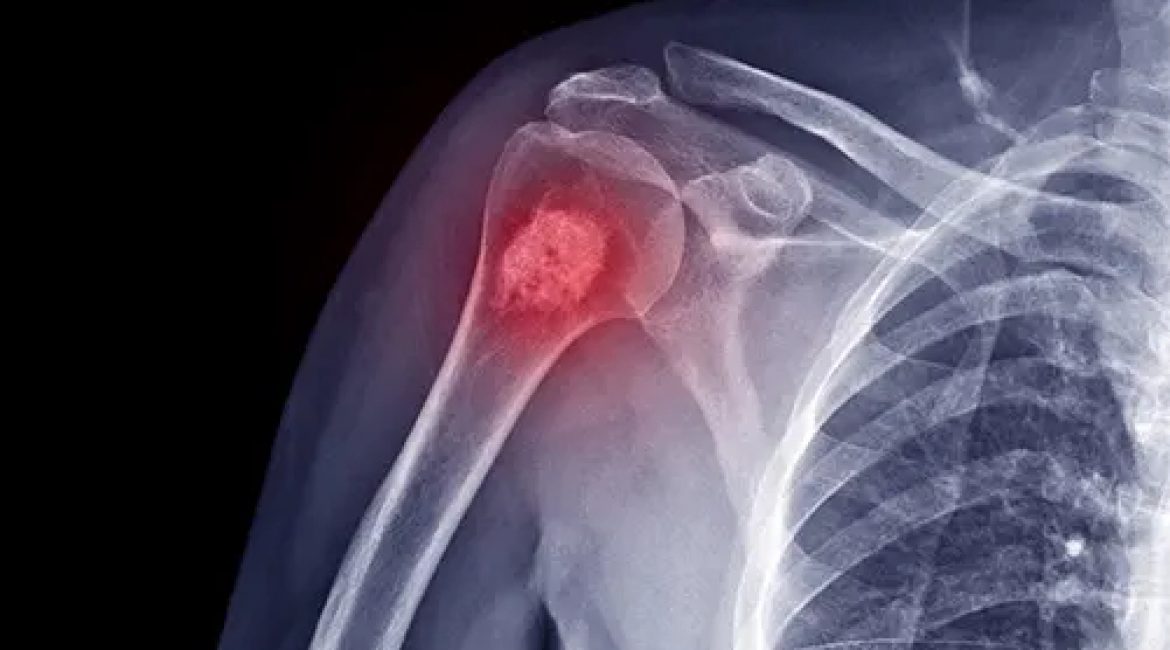

Ο πόνος στον ώμο είναι αρκετά συχνός στην ενήλικη ζωή και υπάρχουν πολλές δομές στον ώμο